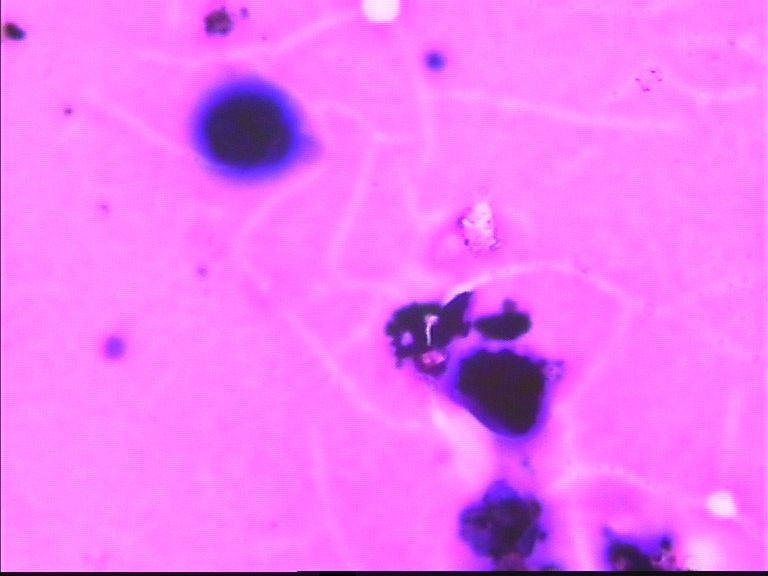

67岁胸水,有风湿病

深染的不是细胞(就是细胞,看不到结构,也不能诊断)。

看不清,不能诊断

制片质量欠佳,直接就看不出是什么了!

这些深染的是什么东西呢?好奇怪

深染的东西像杂质

深的可能是染料渣子

如果怀疑深染的东西里有细胞,那就加热加盖片的位置,取去盖玻片,在二甲苯里溶去封固胶,从高浓度到低浓度的酒精去掉二甲苯,直至水洗,再进入盐酸酒精里,再分化一会儿,看颜色退去些后,能不能看见有细胞结构。目前确实什么都看不见,也说不了什么。

没看出有设么异常细胞   图20好像有霉菌菌丝